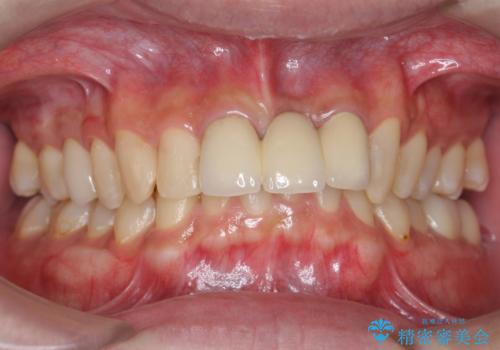

- 以前、前歯にボールが当たりダメになってしまって抜歯したが、そこにとりあえず接着剤で歯をつけて生活していたとのこと。

両側の歯の接着剤の周りが虫歯になってしまっていました。

両側の歯の虫歯をしっかりとってブリッジにすることにしました。

欠損部に長年薄いプラスチックの仮の歯を留めていたため、下の歯が食い込みさらにブリッジのポンティックの隙間がない状態でした。そのため、かみ合わせが深く、下の歯との隙間がかなりなかった為、事前の矯正治療をお勧めしましたが、希望されず特に行わずそのまま虫歯治療を行うことになりました。

- 33万円(仮歯1万円x3 メタルボンドクラウン 9万円x3 プレミアムナイトガード 3万円)費用は治療当時の料金となります

かみ合わせが深く、歯ぎしりでブリッジに負担がかかるため、ナイトガードを作成し、就寝時使用していただいています。